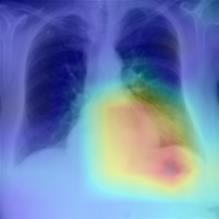

Thoracic disease detection from chest radiographs using deep learning methods has been an active area of research in the last decade. Most previous methods attempt to focus on the diseased organs of the image by identifying spatial regions responsible for significant contributions to the model's prediction. In contrast, expert radiologists first locate the prominent anatomical structures before determining if those regions are anomalous. Therefore, integrating anatomical knowledge within deep learning models could bring substantial improvement in automatic disease classification. This work proposes an anatomy-aware attention-based architecture named Anatomy X-Net, that prioritizes the spatial features guided by the pre-identified anatomy regions. We leverage a semi-supervised learning method using the JSRT dataset containing organ-level annotation to obtain the anatomical segmentation masks (for lungs and heart) for the NIH and CheXpert datasets. The proposed Anatomy X-Net uses the pre-trained DenseNet-121 as the backbone network with two corresponding structured modules, the Anatomy Aware Attention (AAA) and Probabilistic Weighted Average Pooling (PWAP), in a cohesive framework for anatomical attention learning. Our proposed method sets new state-of-the-art performance on the official NIH test set with an AUC score of 0.8439, proving the efficacy of utilizing the anatomy segmentation knowledge to improve the thoracic disease classification. Furthermore, the Anatomy X-Net yields an averaged AUC of 0.9020 on the Stanford CheXpert dataset, improving on existing methods that demonstrate the generalizability of the proposed framework.